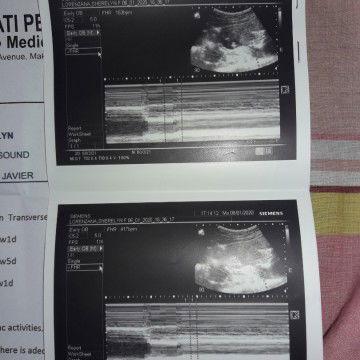

My Pelvic Ultrasound when i was 3months preggy

Lying in clinic private 1300pesos